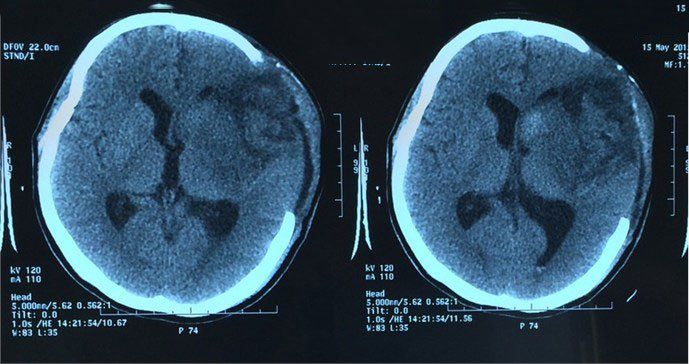

Người bệnh phù não có thể được chẩn đoán chính xác ngay khi phát hiện các triệu chứng trê bằng cách thăm khám và kết hợp các phương pháp chẩn đoán cận lâm sàng hiện đại khác như: Khám thực thể đầu và cổ, thần kinh, chụp CT hoặc MRI sọ não, xét nghiệm máu.